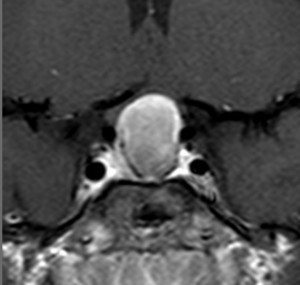

左と中央の画像でinfundibular recessの管腔が見え,左の視交差から視索の変形が強いことが解ります。右の画像では下垂体組織がトルコ鞍の右側に偏在してあります。画像では正常化錐体と明瞭な境界があるように見えるのですが,実際の手術所見では正常下垂体との境界は不鮮明でした。腫瘍のう胞からは黒褐色の内容液 machinery oil とコレステリン結晶が流出しました。厚いのう胞壁は硬膜と下垂体に強く付着して剥離するのが困難で切断して摘出しました。ラトケのう胞とはのう胞壁の厚さが異なると言えます。

術後5ヶ月のMRIです,無理して全摘出しませんでしたので残存腫瘍のように見えます。病理診断では,出血,慢性炎症性細胞浸潤を伴い,コレステリン結晶やヘモジデリンの沈着,泡沫組織球,多核巨細胞浸潤を伴った繊維性組織片に,少量の上皮組織塊があり,少量の正常下垂体組織も付着していると報告されました。施設によってはこの所見をラトケのう胞と病理診断するかもしれません。

術後には軽度の尿崩症がでましたが,1年半でデスモプレッシンを中断できて,下垂体機能は正常化しました。

1年半を要して残存腫瘍は徐々に縮小しました。この画像は術後3年半のもので,正常下垂体がトルコ鞍右側に偏って見えます。